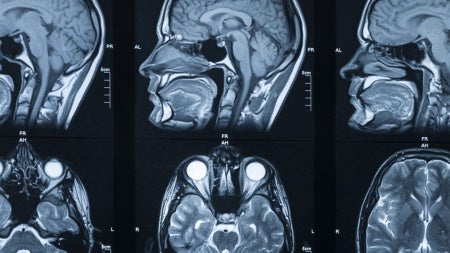

Participants will take a deep dive into the details of the program, the three track options (biochemistry, neuroscience and pharmacology), application requirements and what sets CWRU’s program apart from others.